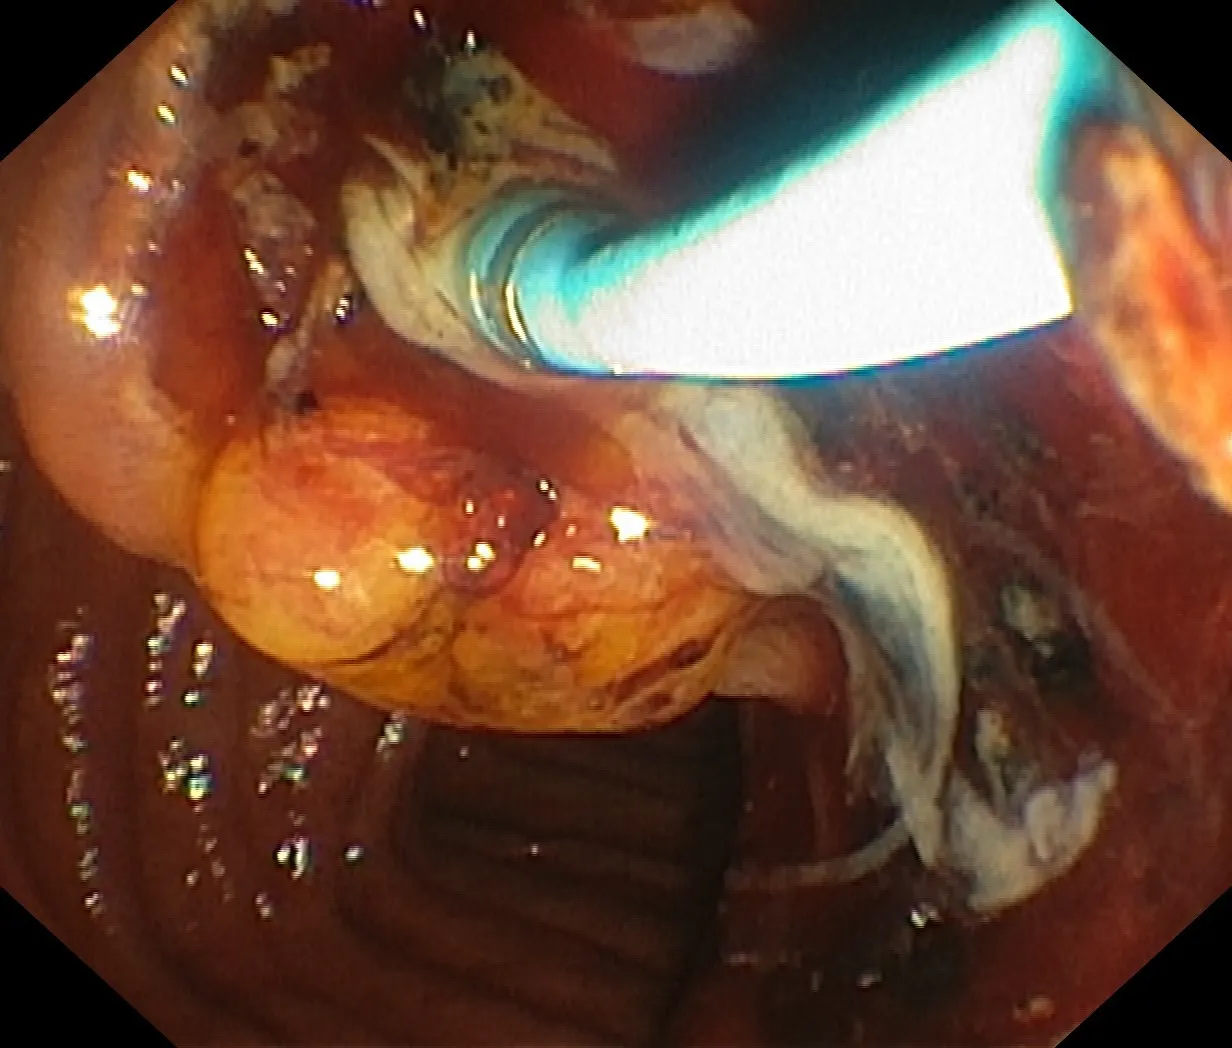

Figure 12: Suppurative (purulent) cholangitis secondary to obstructed bile ducts – the trail of milky liquid is pus resulting from bacterial infection caused by prolonged stone obstruction of the common bile duct. The voluminous pus flow was abrupt following successful cannulation of the ampulla.